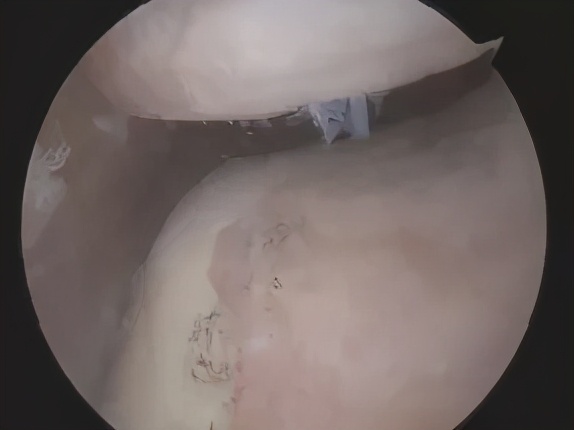

正常的髌股关节

饱经沧桑的髌股关节

如果青少年出现5号位的疼痛,并且有关节内弹响、偶尔关节卡锁的症状,就非常有可能是外侧先天性盘状半月板撕裂。简单来说,就是外侧半月板发育的太大太厚了(亚洲人非常常见),就容易在膝关节扭转时发生撕裂。一旦撕裂,关节功能影响较大,通常需要关节镜手术修复。